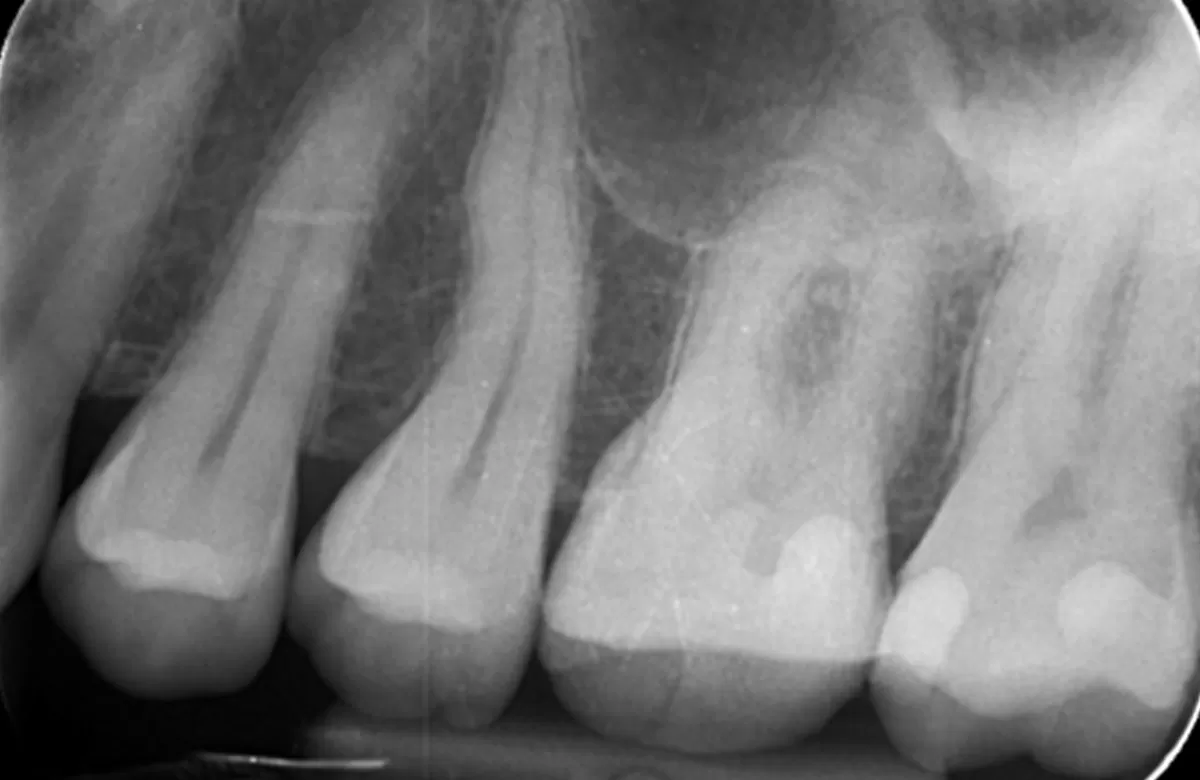

Pre operative periapical radiograph of the tooth 16